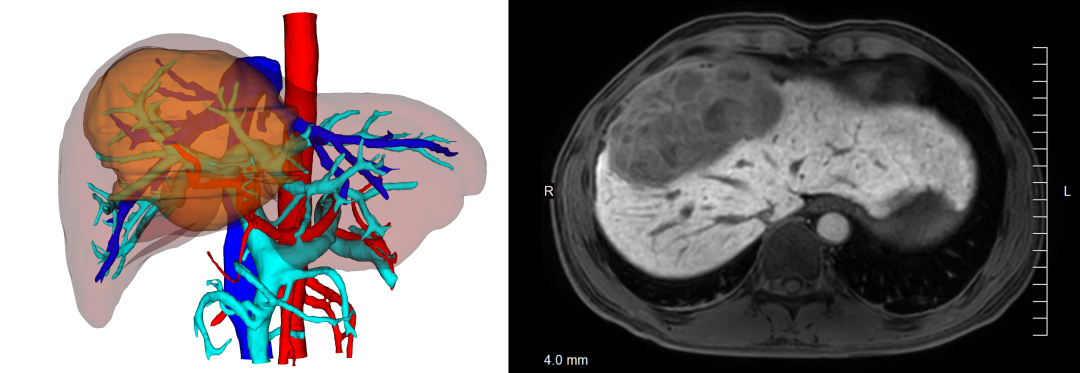

65岁的梁伯没有想到,因为腹胀不舒服就医,却查出了肝脏上一个拳头大小的巨大肿瘤!在珠江医院肝癌诊疗中心,三维可视化技术之下的影像清晰显示:肿瘤大小达13厘米 X 10厘米,盘踞在肝脏的整个中央区域,紧紧贴着肝内大血管,凸出在肝脏膈面并与膈肌形成粘连……这个位置特殊的巨大中央型肝癌让人大吃一惊,梁伯还有手术的机会吗?梁伯的家人揪心不已。

这台手术,微创理念、精确术前规划和实时术中导航贯穿治疗全程,在三维腹腔镜多模实时融合(增强现实)与交互(混合现实)导航技术的加持下,手术视野中,吲哚菁绿(ICG)的荧光对肿瘤和肝中叶边界的界定清晰、精准到了细胞分子的层面;麻醉团队全程稳控中心静脉压,手术医生戴着特制眼镜,病变的肝脏以3D影像呈现在眼前,虚拟的三维肝脏模型叠加在真实肝脏之上,视野缩放、旋转、移动,实时实景导航……“科幻片”一般的场景,出现在现实的手术室里,手术团队高效率地摘除了梁伯肝脏上的巨瘤。术后第8天,梁伯就康复出院了。

数字智能化微创 拯救更多晚期患者

相比二维 CT 影像图,三维可视化模型清晰显示巨块型肝癌及其与肝脏脉管关系